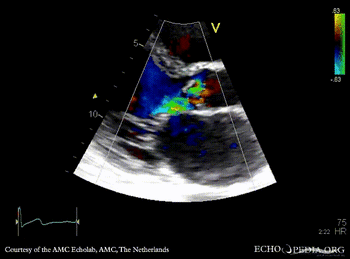

PLAX: vegetations on aortic valve, dilated left ventricle and left atrium PLAX: Color Doppler, severe aortic regurgitation, excentric jet, and moderate mitral regurgitation